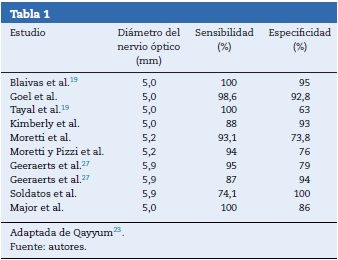

Para la mayoría de los autores revisados 5 mm es el punto de corte para que el estudio se considere positivo para hipertensión endocraneana; otros autores proponen valores diferentes (tabla 1).

Se resalta una revisión sistemática publicada en 2011 de Dubourg et al.33 y que evaluaba la precisión diagnóstica de la medición del nervio óptico en comparación con la medición invasiva de la presión intraparenquimatosa como el estándar de oro; se incluyeron 6 estudios prospectivos de cohorte con un total de 231 pacientes sin detectarse heterogeneidad significativa para la sensibilidad y la especificidad de la medición ultrasonográfica33. La medición de la vaina del nervio óptico tiene una sensibilidad de 0,90 (IC 95%: 0,80-0,95) una especificidad de 0,85 (IC 95%: 0,73-0,93). Esta revisión también mostró una fiabilidad entre los evaluadores de 0,2 a 0,3 mm. Su inconveniente es que no se contó con un valor de corte preciso para definir la dilatación de la vaina del nervio óptico en todos los estudios. La medición del diámetro de la vaina del nervio óptico demuestra buena precisión diagnóstica para detectar la hipertensión intracraneal e influye en la decisión de remitir a los pacientes a centros especializados33.

Existen detractores de la medición del nervio óptico en hipertensión endocraneana34. Sin embargo, hasta ahora la falta de correlación no parece ser con la técnica o el proceso fisiopatológico sino por no contarse con un valor de corte estándar que sugiera el límite entre la normalidad y la hipertensión35. También es necesario estandarizar la técnica de escaneo, teniendo en cuenta que el ojo es una esfera y virtualmente podría realizarse longitudinal o trasversalmente sin conocerse qué tanto podría alterar los resultados24,35-37.